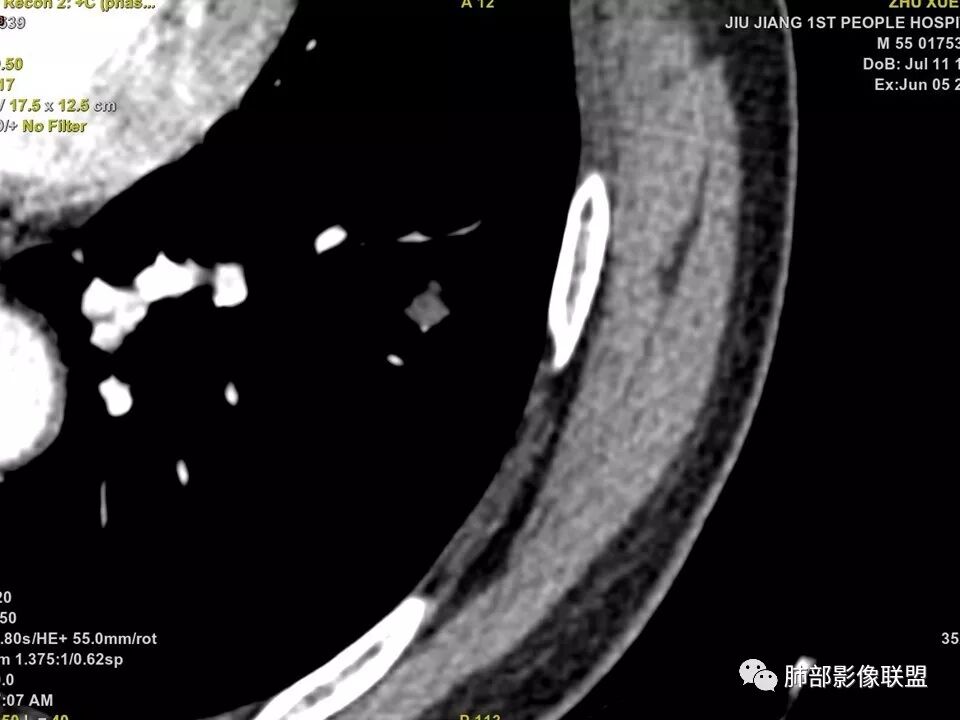

中年男性,左肺下叶不规则实性结节,有分叶及棘状凸起,支气管截断,轻度不均匀强化,考虑鳞癌,鉴别炎性肉芽肿。

左肺下叶前内基底段结节 深分叶和脐凹 表面部分膨隆 部分收缩 支气管截断 轻度强化 中央有坏死 考虑鳞癌 鉴别炎性结节

中年男性,支气管门口截断、邻近支气管未见管壁增厚,分叶明显,边缘彭隆,内见小坏死灶,周围未见GGO,考虑周围性鳞癌,鉴别炎性肉芽肿。

边缘有光滑,有圈黑晕,强化弱,似乎有脂肪密度,支气管截断的部位很自然,没有鼠尾状狭窄,考虑软骨型错构瘤?

这个支气管开口位置,如果是肿瘤应该有管壁浸润,也应该有膨胀感,这个没有,不像恶性肿瘤的支气管截断

典型CT特征包括:(1)圆形或椭圆形边界清楚的病灶。(2)大小1~4cm,有轻微分叶改变。(3)较均匀的软组织影,多伴有钙化。(4)无毛刺,卫星灶及肺门或纵隔淋巴结肿大。(5)CT增强扫描无强化或轻度强化,其强化可能与软骨瘤间质中的薄壁血管或周围慢性炎症反应有关。